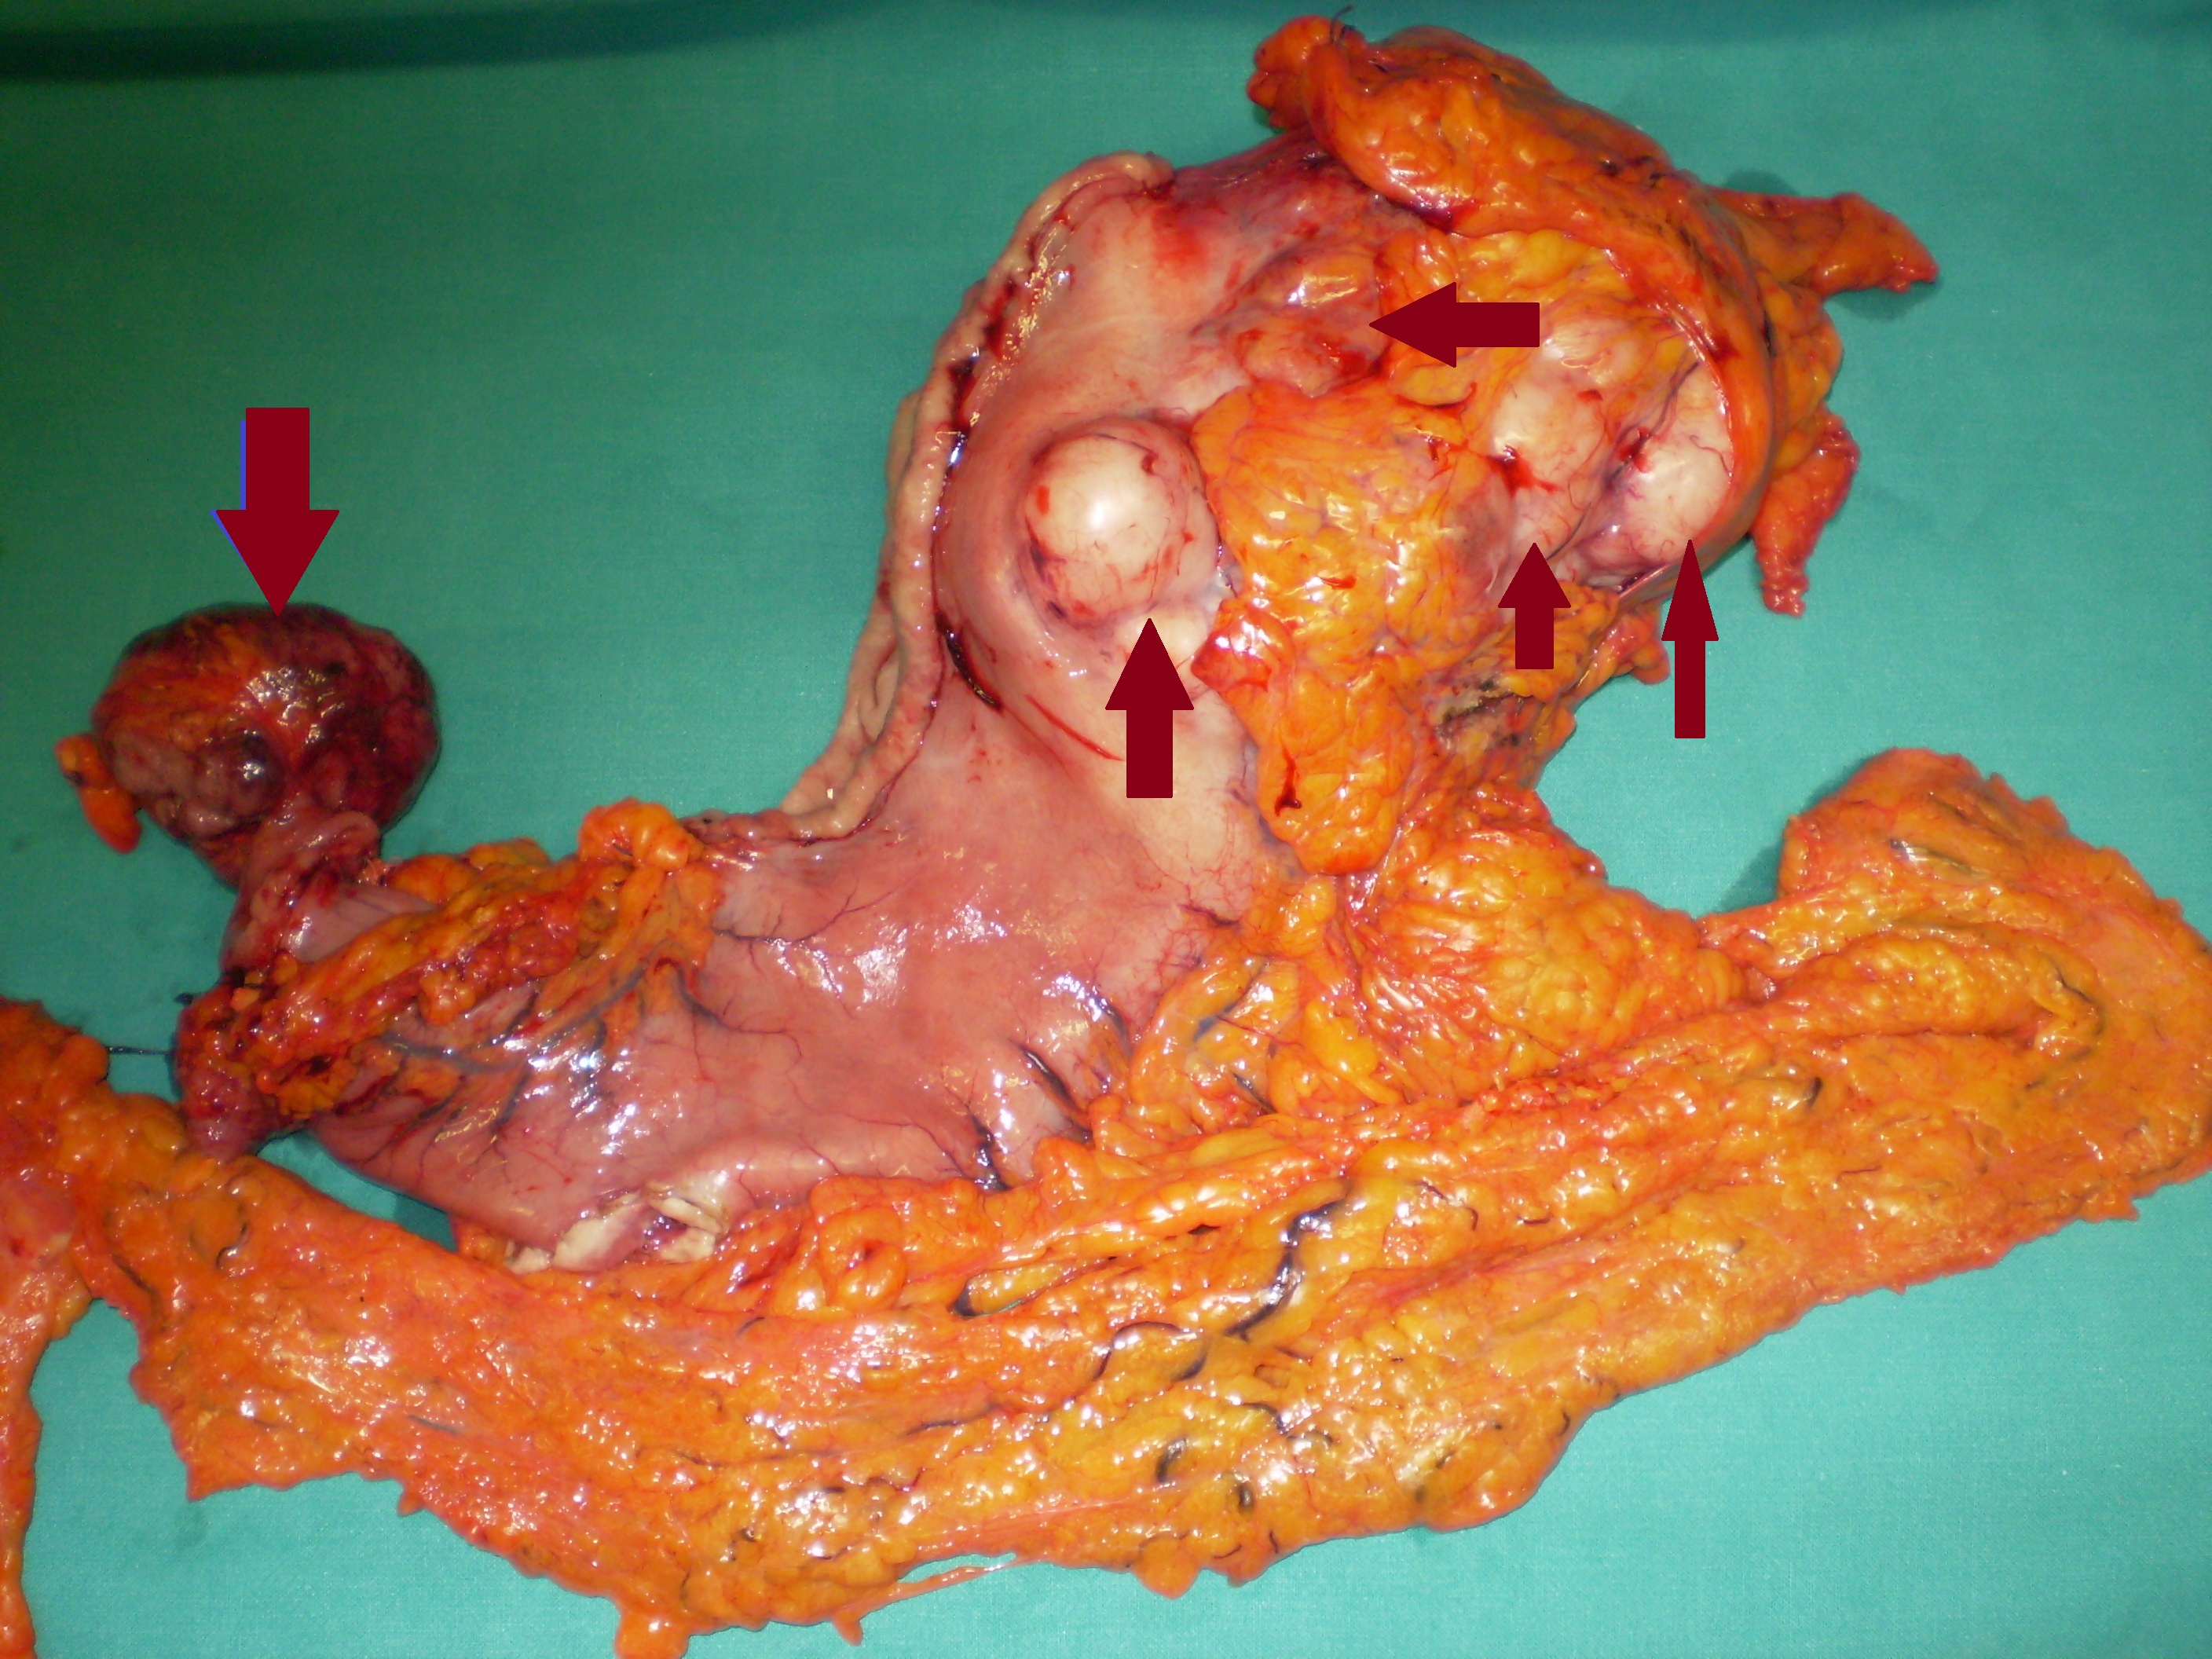

Total gastrectomy specimen. Brown arrows – Multiple gastric stromal tumors (Courtesy Dr. V. Penopoulos)